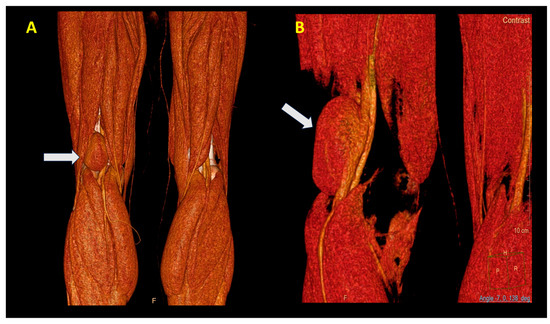

The surgical procedure was conducted with the patient positioned in the ventral decubitus position. Given the substantial size of the popliteal vein aneurysm (60 mm, Figure 4A), circumferential dissection was deemed unfeasible, necessitating a posterior-wall surgical approach (Figure 4B). The vascular control was achieved by clamping both the proximal and distal ends of the aneurysm. Additionally, to reduce venous inflow from the distal segment, the popliteal artery was clamped.

Figure 3. View of the PVA (white arrow). (A) Posterior and (B) lateral view. Note the large dimensions (60 mm).